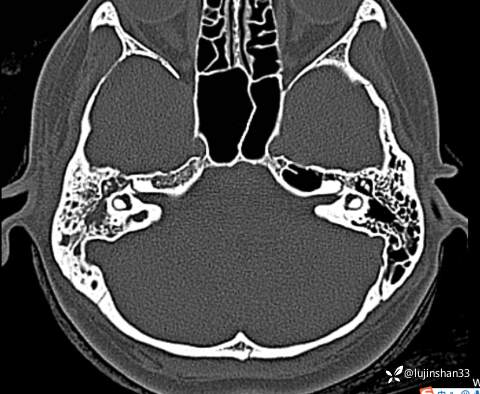

颞骨CT: